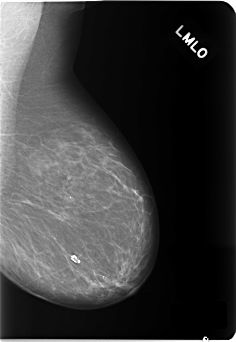

C_0140_1.LEFT_CC

LEFT_CC LINES 5856 PIXELS_PER_LINE 3280 BITS_PER_PIXEL 12 RESOLUTION 50 NON_OVERLAY